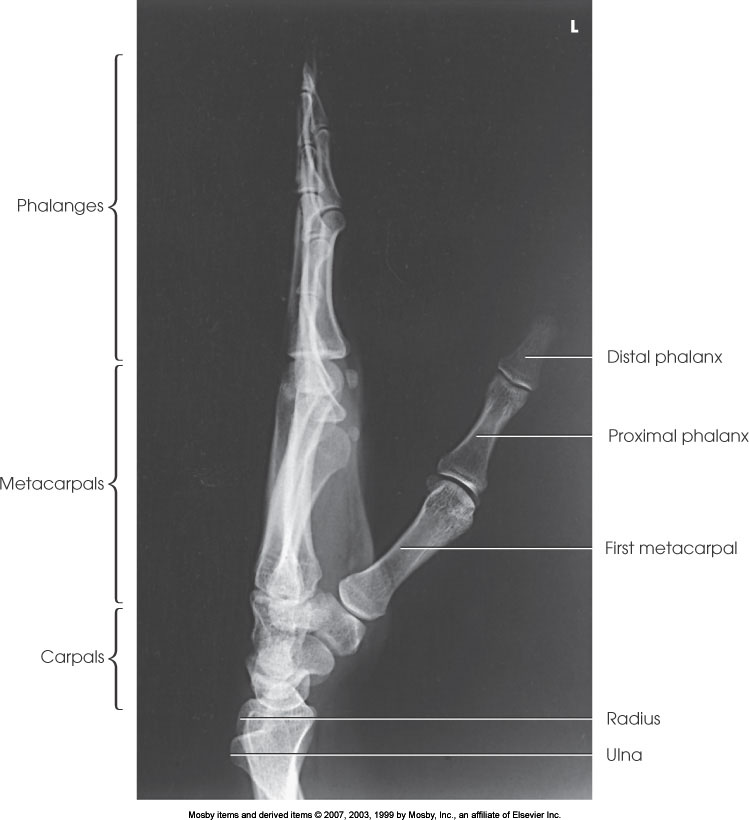

Lateral Hand

What position is demonstrated?